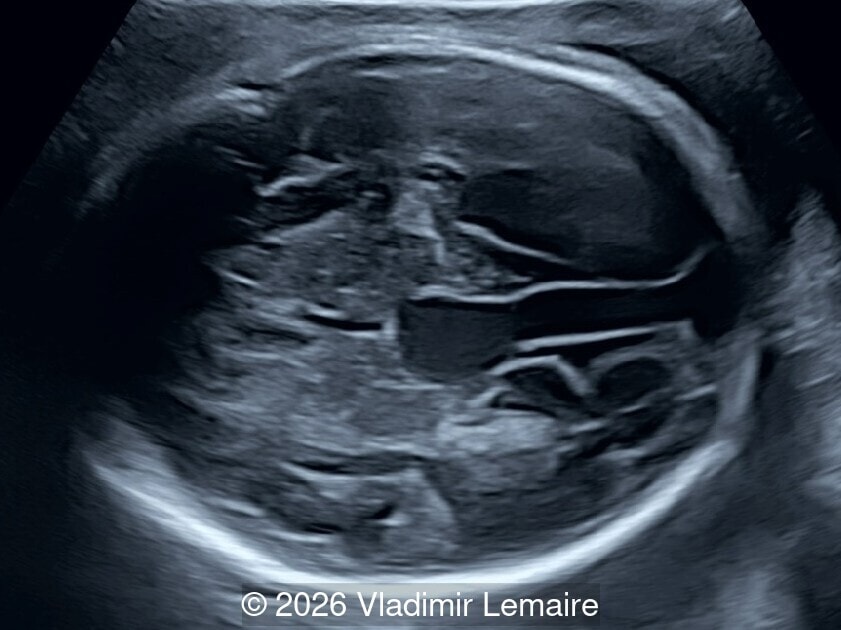

The five-chamber view.

Image 3 The five-chamber view.